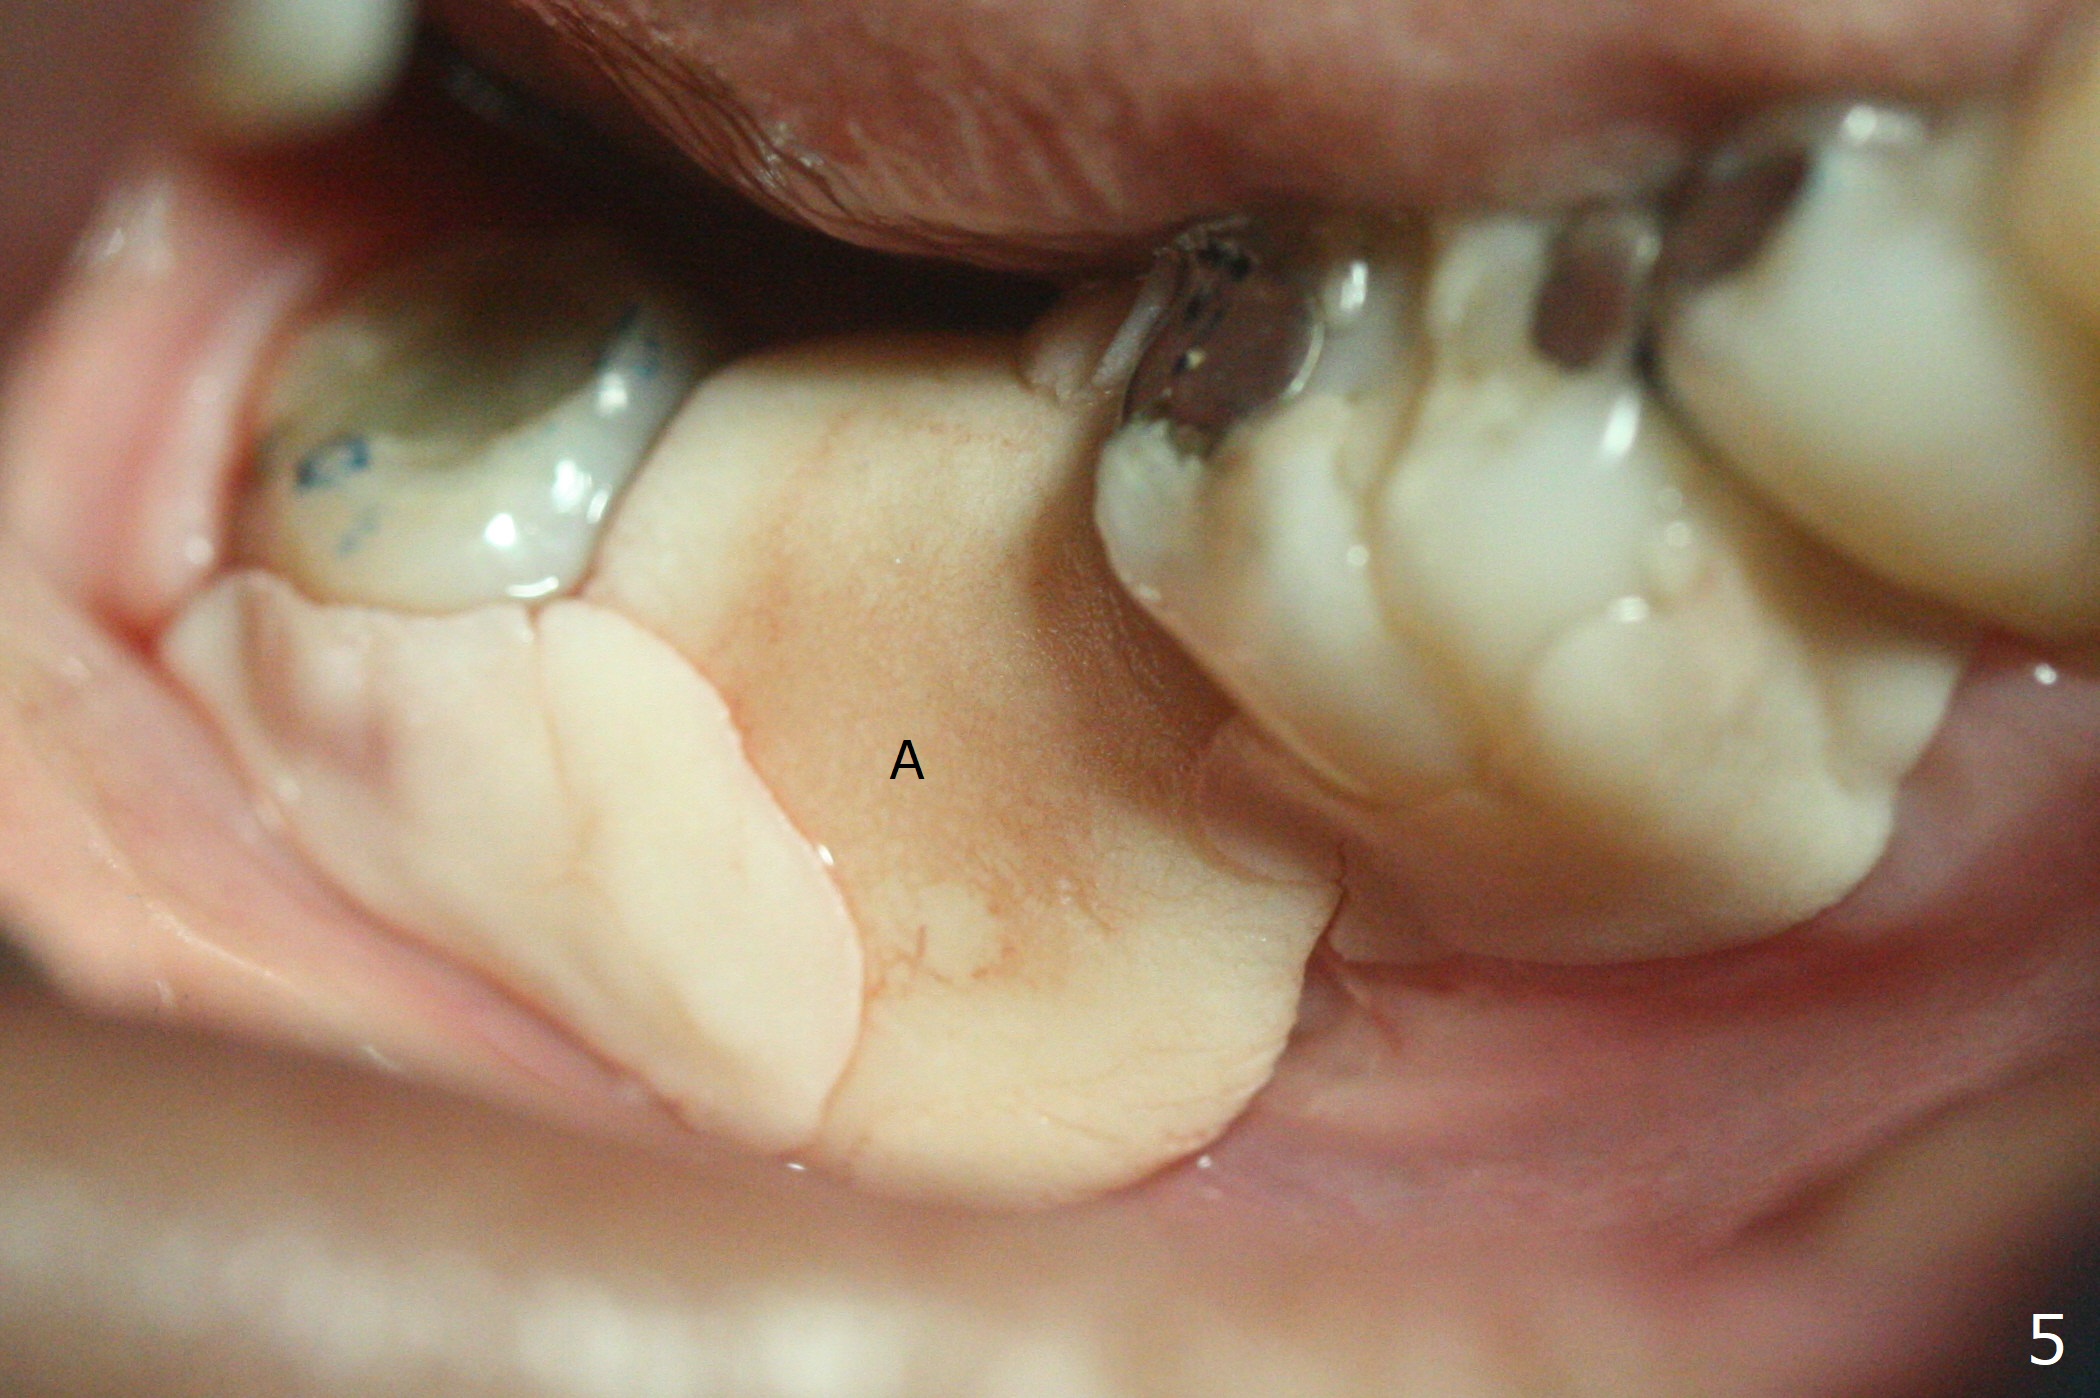

In fact the buccal gingival recession at #31 is asso-ciated with cervical caries perfor-ation (Fig.1 P). The debrided socket is packed with mine-ralized cortical: cance-llous mix (50:50) (better using mine-ralized cortical allograft (future particle size: 125μm – 850μm)) hydrated with ~ .25 ml of .3 mg/ml of rhPDGF-BB (one compo-nent of GEM21S, Fig.2,3). It is extremely difficult to close the socket opening with buccal defect with Osteogen Plug, 12x12 mm BioXclude and 4-0 PGA suture (Fig.4). Acrylic dressing is unstable in spite of several reline (Fig.5 A). Its replace-ment is GEM Cap RCM (regenerative collagen membrane), 9-12 month resorption time, which will be fixed in place with Perio Glue. Watch Video. In fact, 2 pieces of the reline dislodge in the 1st 2 days postop, while the whole piece 3rd days postop. The patient feels better when the acrylic dressing is out. It appears that the bone graft does not fall out, according to phone visit during coronavirus outbreak. A third method to close the buccal defect is to make mesial and distal release incisions (Fig.6) and transfer the flaps (Fig.7). In fact the bone graft gets lost, revealed over phone. Immediate implant is the most secure method to keep the bone graft. PRF may be more retentive. The fourth way is to place Cytoplast, which is fixed with spacer and periodontal dressing.